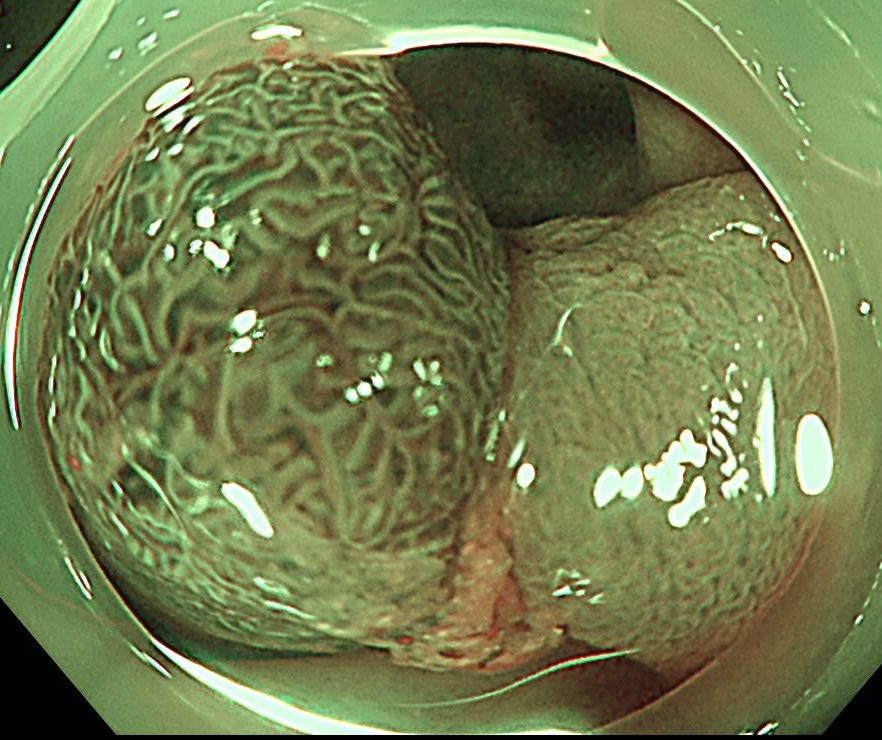

横行結腸に1型の腫瘍を認めます。

ピットパターンはおおむねIII型ですが、腫瘍基部と中心陥凹部はV型であり、早期の大腸がんが疑われます。